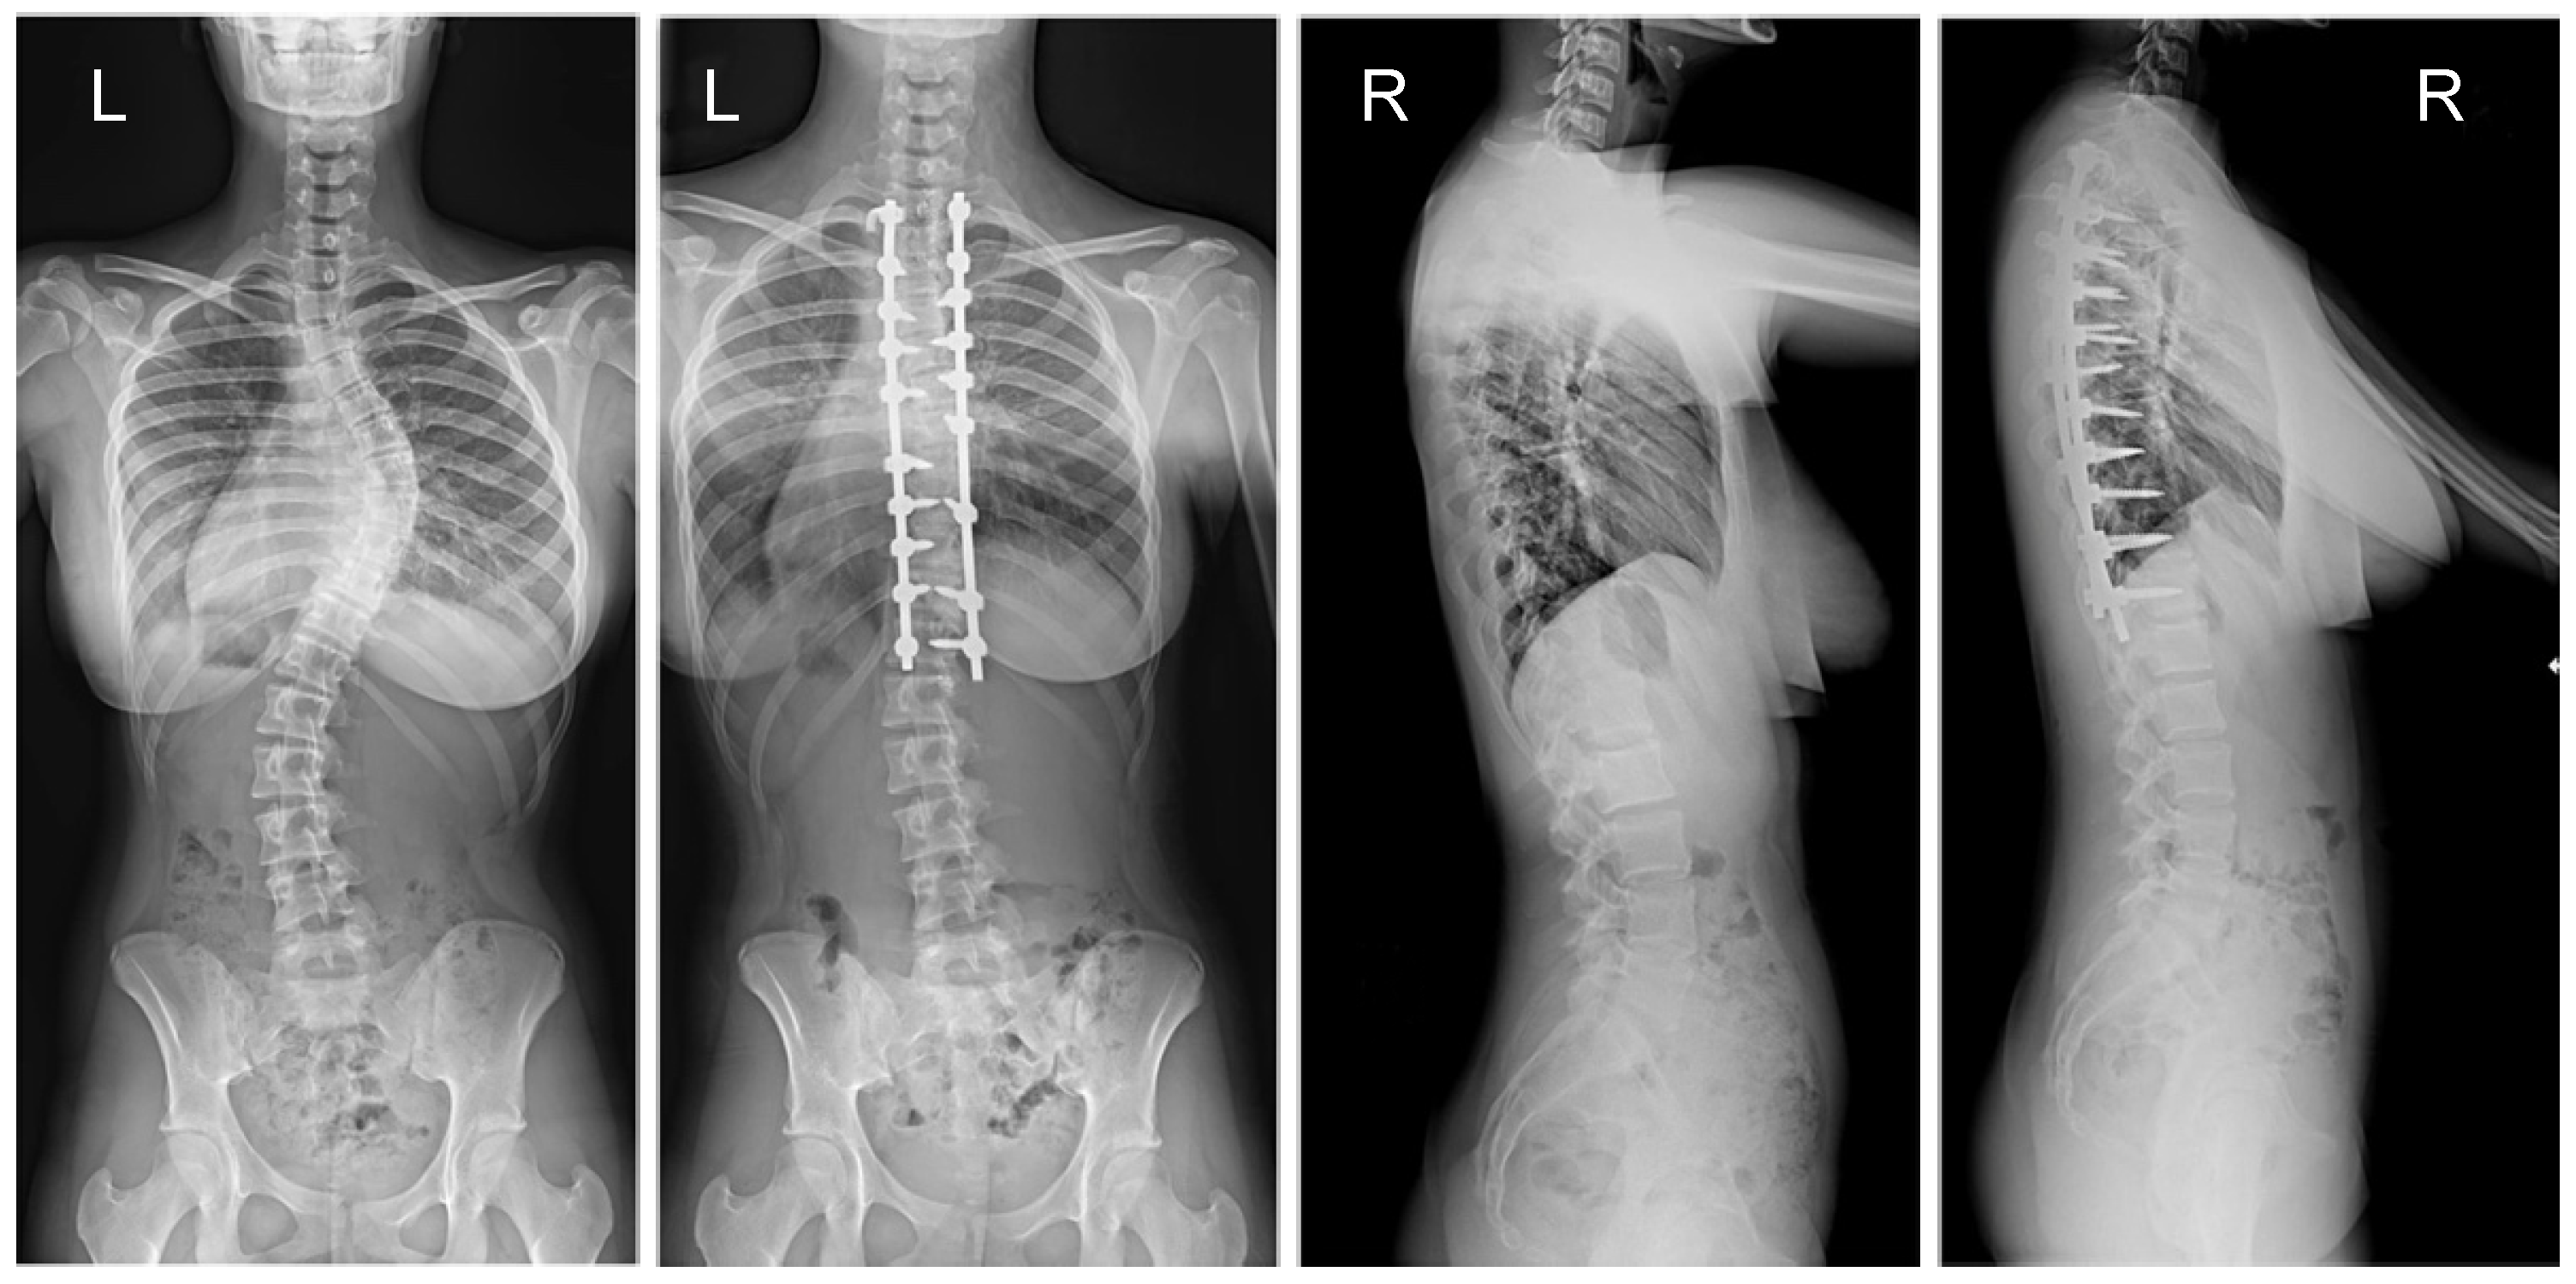

Figure 1.

X-rays of an 18-year-old girl with AIS, treated with selective thoracic fusion. A larger screw size of 6.5 mm and 2 cobalt–chromium rods of 6.0 mm were used (G2). X-rays show curve before surgery and correction after surgical treatment.